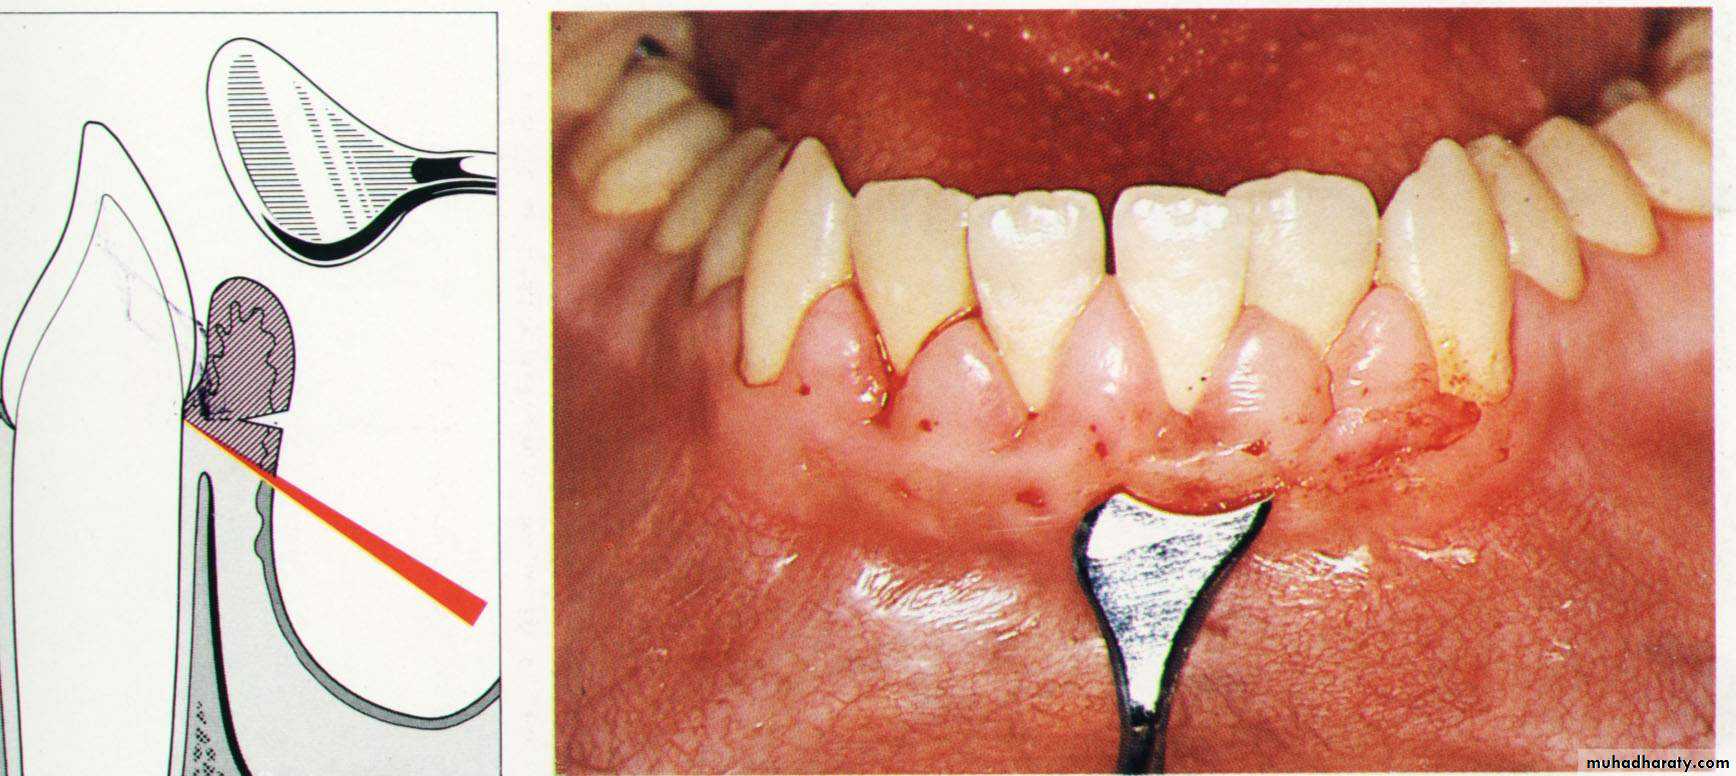

The minor alterations in gingival morphology usually termed gingivoplasty while the procedures that compromised a major amount of gingival tissues termed as gingivectomy.Goldman gingivectomy procedure:

1. Giving of local anesthesia.

2. Determination of the bleeding points by using the pocket depth marker.

Primary beveled incision, which carried out according to the bleeding points.

4. Secondary incision to separate the interproximal soft tissues form the

interdental periodonteum.5. Careful removal of the incised tissues by a curette or a scalar.

6. The bleeding can be controlled by a gauze pack inter proximally.

& performing of a careful scaling for the exposed root surface.7. Adjustment of the gingival contour & checking of the dentogingival area.

8. Dressing of the wound for (7 – 10 days).

9. Dressing removal & polishing.